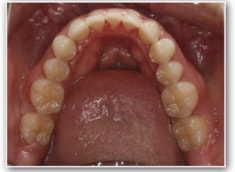

治療前